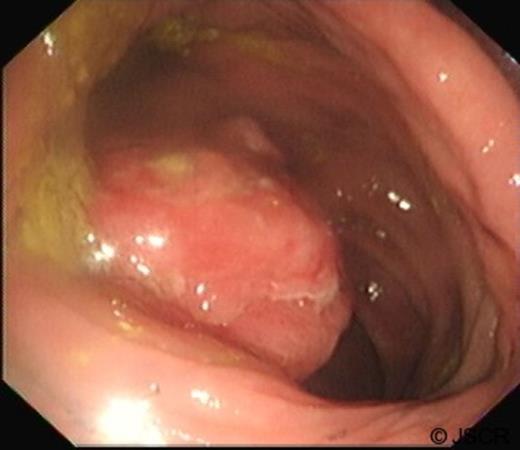

A 74 year old man with a background of Chronic Obstructive Airways Disease (COAD) was referred for urgent assessment by his general practioner with a 1 month history of lower abdominal pain and altered bowel habit. Faecal occult blood testing was positive. Abdominal and rectal examination was unremarkable and routine blood testing including carcinoembryonic antigen (CEA) was normal. He underwent urgent colonoscopy which was complete to the caecum. A large ulcerating polypoidal lesion was found at his hepatic flexure (Figure 1).

Colonoscopy demonstrating large pedunculated ulcerating lesion found at hepatic flexure